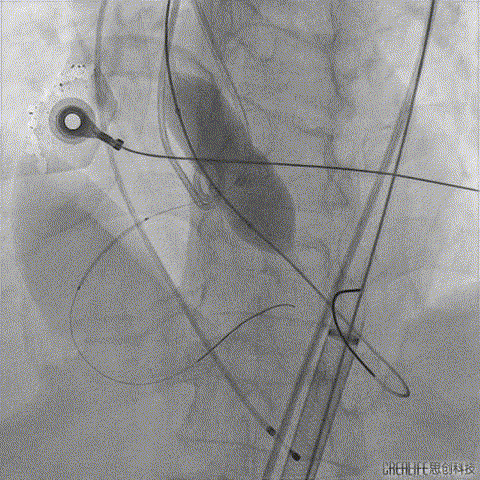

术前CT分析右侧的冠脉风险较高,球囊预扩前右冠开口处预放一个冠脉保护支架,采用18mm球囊预扩,有轻微腰征,无造影剂渗漏;

右侧冠脉保护准备

球囊预扩

TaurusElite输送系统轻松过弓、跨瓣,AV23瓣膜瓣环上约2mm释放;

TaurusElite轻松过弓

瓣膜释放